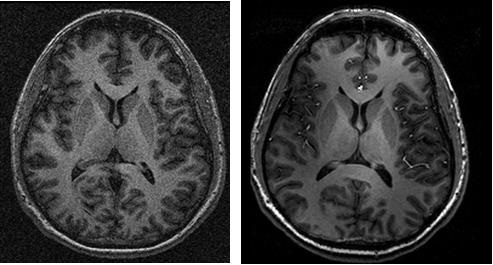

MRI Image Quality Compared at 3T and 3T

MRI image quality compared at 3T and 7T using nearly identical acquisitions and quadrature transmit volume radiofrequency coils.  Signal/noise is improved ~2x at 7T compared to 3T. (Rooney and Grinstead).